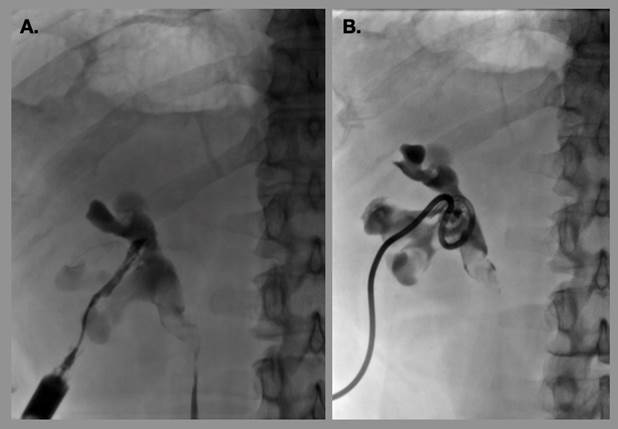

Los recambios se recomiendan cada 3 meses. En el caso de dejar un catéter doble J, estos pacientes son referidos con el servicio de urología para la realización del recambio endourológico, que se aconseja en un periodo de 4 meses. En caso del estent nefroureteral y del catéter de nefrostomía se debe ser muy cauteloso en agendar las citas de recambio, ya que la incrustación de un catéter puede asociar a formación de litos que desarrollen un episodio de litiasis posterior al recambio (Figura 2) que dificulten el recambio de catéter (Figura 3 y 4) o incluso impidan la remoción de este por guía fluoroscópica, dejando como única opción la remoción quirúrgica.6

(A) Se muestra imagen de control por retiro de catéter y recanulación del trayecto mediante opacificación de este con medio de contraste. Se avanza guía a través del trayecto trazado y se coloca nuevo catéter (B).

Figura 3 Paciente portador de nefrostomía derecha por más de 6 meses sin recambio del catéter